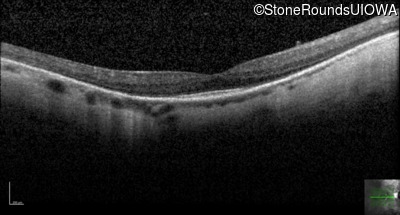

Optical Coherence Tomography - Right - 20/25

Exemplar / OCT Stack

OCT Stack